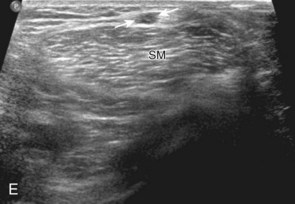

Thigh Evaluation: Posterior

Structures of interest in the posterior thigh include the semimembranosus, the semitendinosus, the biceps femoris, and the sciatic nerve. Ultrasound evaluation can begin in the transverse plane at the level of the mid-thigh, or more proximally at the horizontal gluteal crease or ischial tuberosity. At the level of the mid-posterior thigh (Fig. 6-20A), three distinct muscles can be identified medial to lateral, which are the semimembranosus, semitendinosus, and biceps femoris muscles (see Fig. 6-20B). The short head of the biceps femoris can be identified deep to the long head at the femoral cortex at the level of the mid-femur. When the transducer is moved in the transverse plane distally toward the knee, the semitendinosus becomes a thin tendon and moves directly superficial to the semimembranosus muscle (see Fig. 6-20B to D). This is an additional finding that aids the identification of the posterior thigh muscles. In the mid-thigh, the honeycomb appearance of the sciatic nerve can be identified between the biceps femoris muscle and the semitendinosus muscle (see Fig. 6-20B).